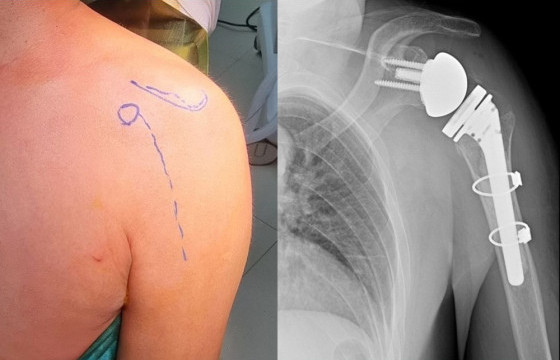

Ч.БЭХ: МОНГОЛД ХОВОР ХИЙГДДЭГ ХҮЗҮҮНИЙ ГИЛЖГИЙ ЗАСАХ ХАГАЛГААГ ТӨЛБӨРГҮЙ ХИЙЖ, ҮҮНЭЭСЭЭ ХАМГИЙН САЙХАН МЭДРЭМЖ АВДАГ

Ч.БЭХ: МОНГОЛД ХОВОР ХИЙГДДЭГ ХҮЗҮҮНИЙ ГИЛЖГИЙ ЗАСАХ ХАГАЛГААГ ТӨЛБӨРГҮЙ ХИЙЖ, ҮҮНЭЭСЭЭ ХАМГИЙН САЙХАН МЭДРЭМЖ АВДАГ

2026-03-26 07:33:13